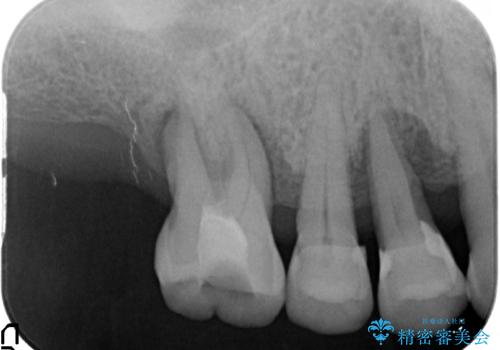

- 「歯がぐらぐらして噛めない、歯を抜いて欲しい、またしっかりと噛めるようになりたい。」、と歯周病治療を希望され来院されました。

歯の根本まで骨吸収が進み、ぐらぐらになってしまった歯を抜去し骨の造成を行ったのちインプラント治療を計画します。